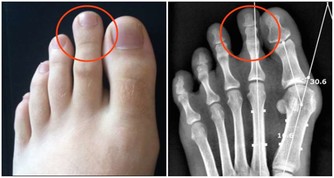

蜘蛛痣、硃砂掌

肝硬化患者常在面部、頸、胸、肩、前臂及手背等處出現一些擴張的皮膚小動脈,周圍有向四周輻射的樹枝樣細小分支,形態像一個個小蜘蛛,呈鮮紅色;

與蜘蛛痣發生機制相同的表現是肝掌,就是指手掌連接大、小拇指的兩側(大、小魚際)發紅,細觀有許多紅色斑點,有的呈斑塊狀,紅白相間無規律,如局部加壓會變蒼白,放鬆後恢復原狀,因其發紅又稱“硃砂掌”。